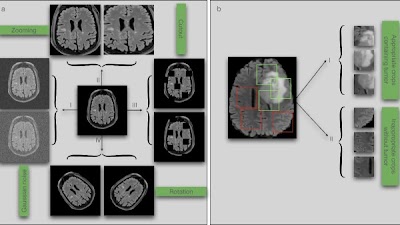

Due to the time-consuming nature of manual segmentation, this study explored potential of deep convolutional #NeuralNetworks as an alternative for fast, accurate segmentation on T1-weighted portal venous #MRI. (Moritz Gross et al.) #EuropeanRadiology 🔗 buff.ly/47K2d8y

Due to the time-consuming nature of manual segmentation, this study explored potential of deep convolutional #NeuralNetworks as an alternative for fast, accurate segmentation on T1-weighted portal venous #MRI. (Moritz Gross et al.)

🔗 buff.ly/47K2d8y